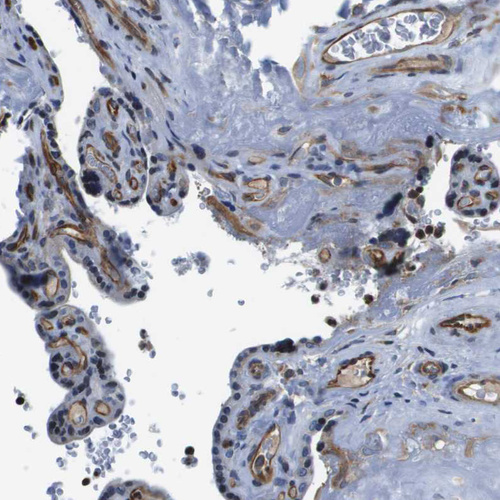

Immunohistochemical staining of human fallopian tube shows moderate cytoplasmic positivity in glandular cells and endothelial cells.